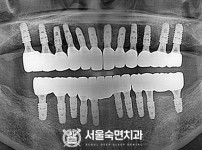

임플란트-전후사진3

치과를-선택할-때-꼭-확인하세요-서울숙면치과-임플란트-전후사진